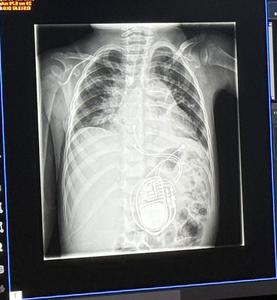

A loop recorder is designed to continuously monitor heart activity for problems. It’s a battery-powered device about the size of a pen cap, implanted under the skin of the chest. And it’s very, very unusual for a two-year-old to have one.

The loop recorder confirmed that Briar’s heart had stopped beating for over two minutes.

“I told Lateishia, ‘Pack your bags.,” Tristani-Firouzi says. “‘You’ve got to come into the hospital, and we’re going to admit you, and we have to put a pacemaker in. Come right now, this is too dangerous to be sitting around at home.’”

Hobbs did surgery to give Briar a pacemaker that would restart her heart if it stopped again, potentially saving her life. He says that, for such a young child, the surgery couldn’t have happened without Tristani-Firouzi’s discoveries to back it up.

“I don’t think that in any other circumstance this child would have gotten a pacemaker,” Dr. Hobbs says. “She went from having the loop recorder to having a permanent pacemaker that can give her heart signals to beat if she has another event like that, because of the research that supported this approach.”